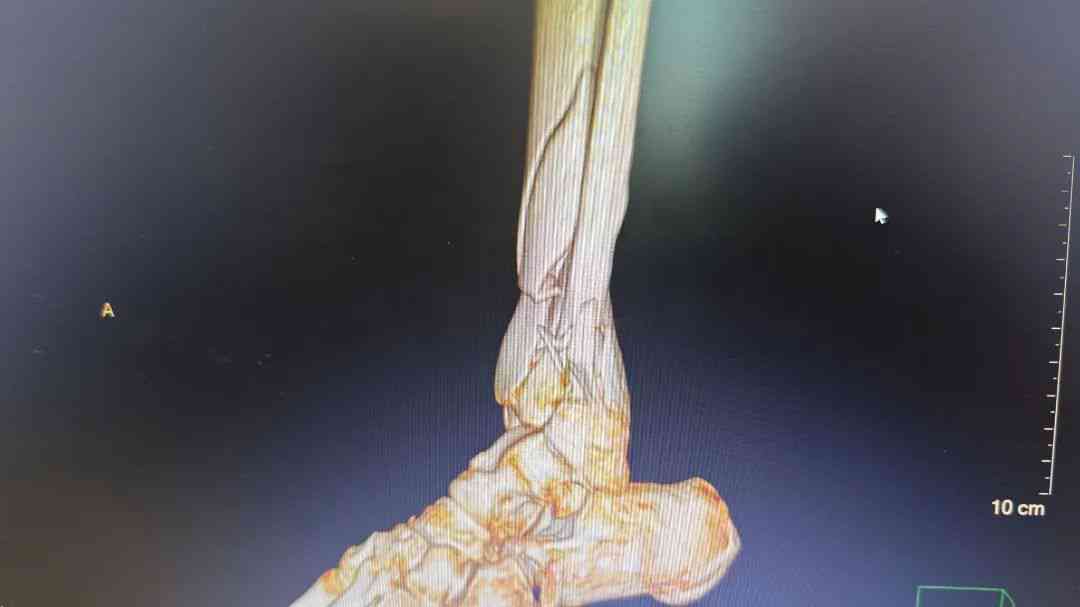

微信图片_20250512172753.jpg 微信图片_20250512172755.jpg 术前腿部影像

经过检查,发现李阿姨小腿明显畸形,骨折成角移位明显,CT显示左胫腓骨远端粉碎性骨折,右胸部7根肋骨骨折合并气胸。